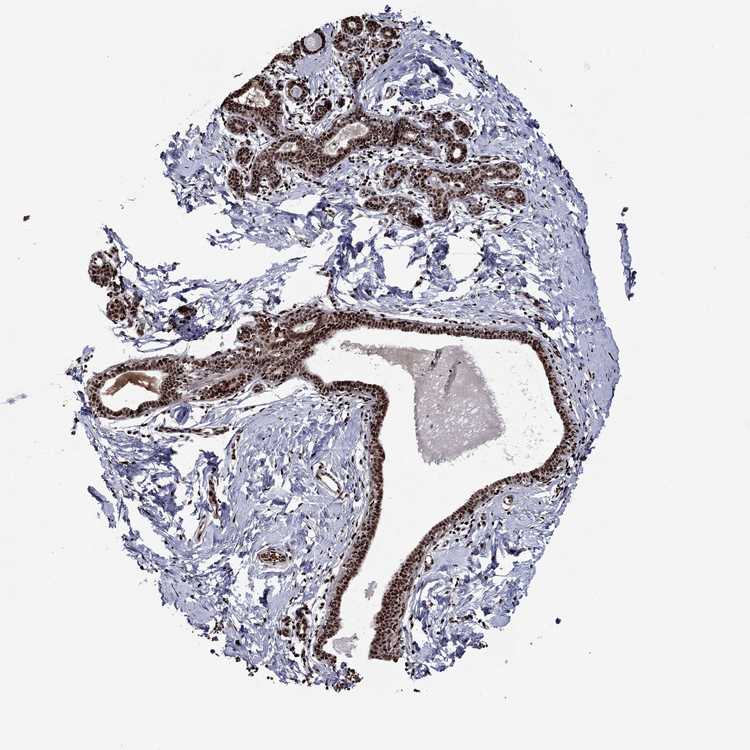

BREAST - Antibody stainingi

Antibody staining in the annotated cell types in the current human tissue is reported as not detected, low, medium, or high, based on conventional immunohistochemistry profiling in selected tissues. This score is based on the combination of the staining intensity and fraction of stained cells.

Each image is clickable and will lead to virtual microscopy that enables deeper exploration of all samples and also displays staining intensity scores, fraction scores and subcellular localization as well as patient and tissue information for each sample.

Antibody HPA028516Antibody HPA073571

Adipocytes LowHigh

Glandular cells HighHigh

Myoepithelial cells HighHigh